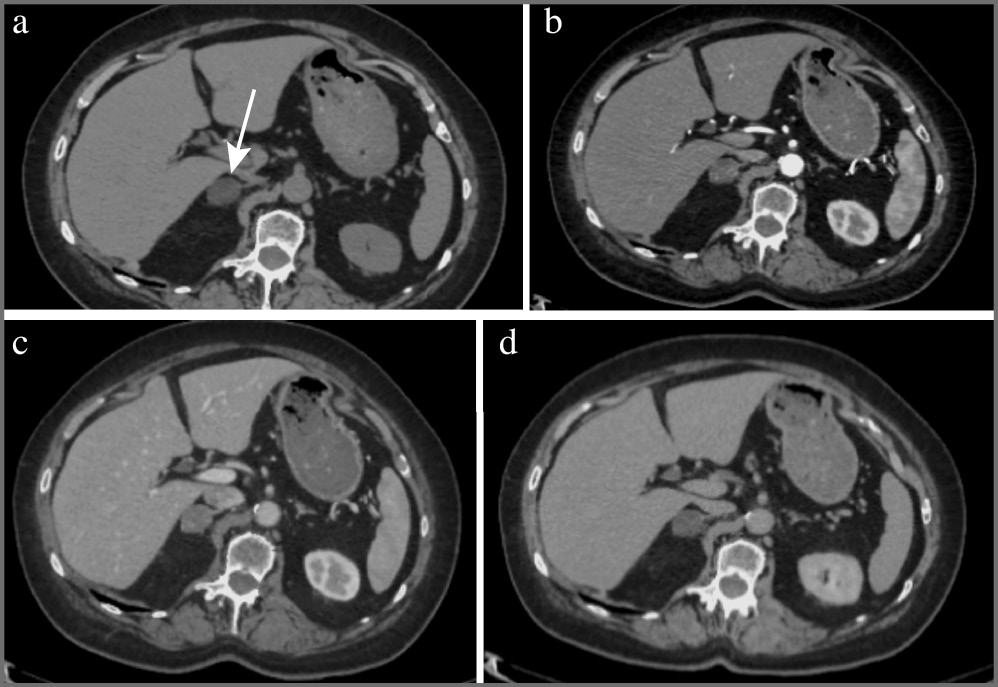

Аденома – доброкачественное образование надпочечника, она составляет около 80% всех образований надпочечников. На КТ-изображениях аденомы обычно представляют собой образования с четкими ровными контурами овальной формы, однородной структуры, размером, как правило, менее 3 см. При динамическом наблюдении размер аденом не меняется или медленно увеличивается в пределах нескольких миллиметров в год (рис. 1) [2].

Рис. 1. Аденома надпочечника с низким содержанием жира (стрелка). МСКТ, аксиальная проекция: а – нативная фаза; b – артериальная фаза; c – венозная фаза; d – отсроченная фаза. Примечание. МСКТ – мультиспиральная компьютерная томография.

В зависимости от количества внутриклеточных жировых включений различают аденомы с высоким (80%) и низким (20%) содержанием жира, что проявляется характерной КТ-картиной. Так, аденомы с высоким содержанием жира представлены на нативных изображениях образованиями плотностью до 10 ед. Н.

Все аденомы имеют патогномоничное накопление контрастного препарата с быстрым «вымыванием» его после внутривенного болюсного контрастирования, что позволяет дифференцировать аденомы с другими заболеваниями надпочечника, например злокачественными новообразованиями и феохромоцитомами.

Для оценки характера контрастирования в большинстве случаев проводится четырехфазное КТ-сканирование с болюсным введением неионного йодсодержащего контрастного препарата со скоростью введения 2–4 мл/с, дозой контрастного вещества с концентрацией 300–350 мг йода/мл (60–76%) не менее 1 мл/кг массы тела пациента (лучше – 100–140 мл). Исследование проводят в нативную, артериальную (18–25 с после начала введения болюса контрастного препарата или 10 с после достижения пика 100–150 ед. Н на болюс-трекере), венозную (55–65 с от начала введения болюса) и отсроченную (15 мин после введения контрастного препарата) фазы. Для аденом максимальное накопление контрастного препарата в большинстве наблюдений определяется в венозную фазу.